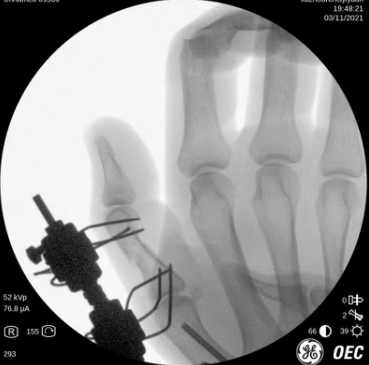

术中透视

术前工作准备完毕,齐伟亚、刘桂谦手术团队为张师傅进行了进行了关节镜辅助下左桡骨远端骨折复位内固定+滑膜清扫,机器人导航下左腕钩状骨骨折复位内固定,左手第1掌骨骨折复位内固定,左拇指近节指骨骨折外固定架外固定,虽然手术时间稍长,但是手术很顺利,术后张师傅恢复良好,张师傅一家称赞齐主任的医技好,而且从患者的角度出发,不让患者多花一分钱。